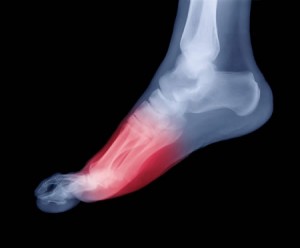

Основной метод диагностики – это рентгенография. Это позволит выявить наличие перелома и его местоположение. Если есть подозрение на разрыв связок или другие повреждения связочного аппарата, то здесь основной метод исследования – это МРТ или КТ.